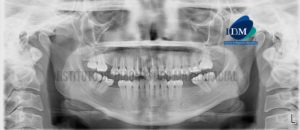

IDM - Radiografía panorámica - idm

226 – Rizogénesis Incompleta

Paciente de 29 años acude al Instituto de Diagnóstico Maxilofacial para evaluación imagenológica de los incisivos centrales. A la evaluación de la radiografía panorámica se